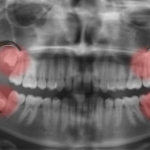

The extraction process begins with an evaluation, often involving X-rays to assess the teeth’s positioning. Local anesthesia or sedation ensures comfort during the procedure. If the tooth is impacted, a small incision is made to access it, followed by careful extraction, possibly in sections. The incision is then closed with stitches if needed.